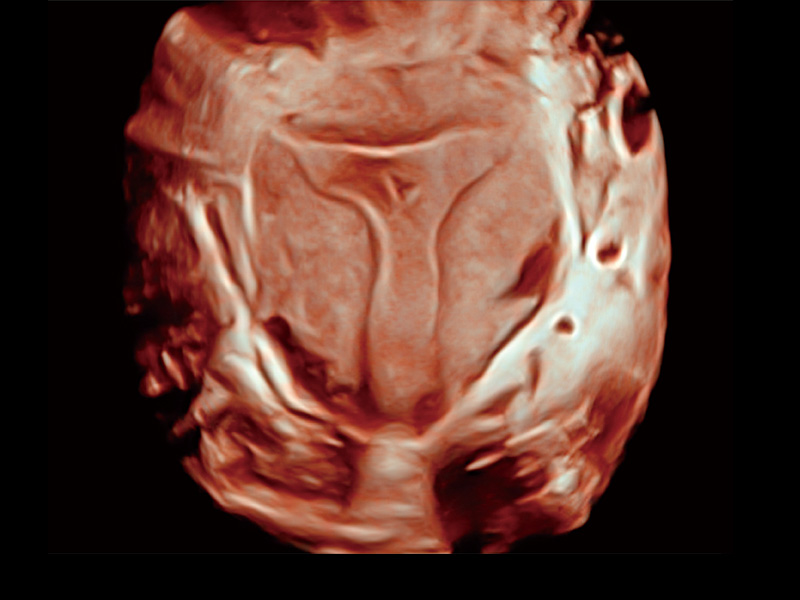

腔内容积探头

腔内三维成像技术获得显著提升,超大扇角在满足日常基础扫查的同时,支持卵泡自动测量及多种三维渲染模式,为您提供更多的诊断信息,尤其是在子宫畸形的诊断,内膜及肿瘤占位观测中起到了重要的作用。

临床图

中央型宫腔粘连

单角子宫